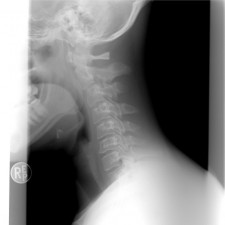

Při dlouhodobé práci je důležité mít nejen správný tvar myši, ale také se umět dobře procvičit. Přínosné je zařazovat pravidelné přestávky tak, aby se uvolnily přetěžované svaly a vazivo. Tyto pauzy je možné vyplnit například cvičením. Vhodná je také správně zvolená léčebně rehabilitační metoda, která se primárně zaměřuje na léčbu pohybového ústrojí především páteře a pomáhá pacientům od bolesti.